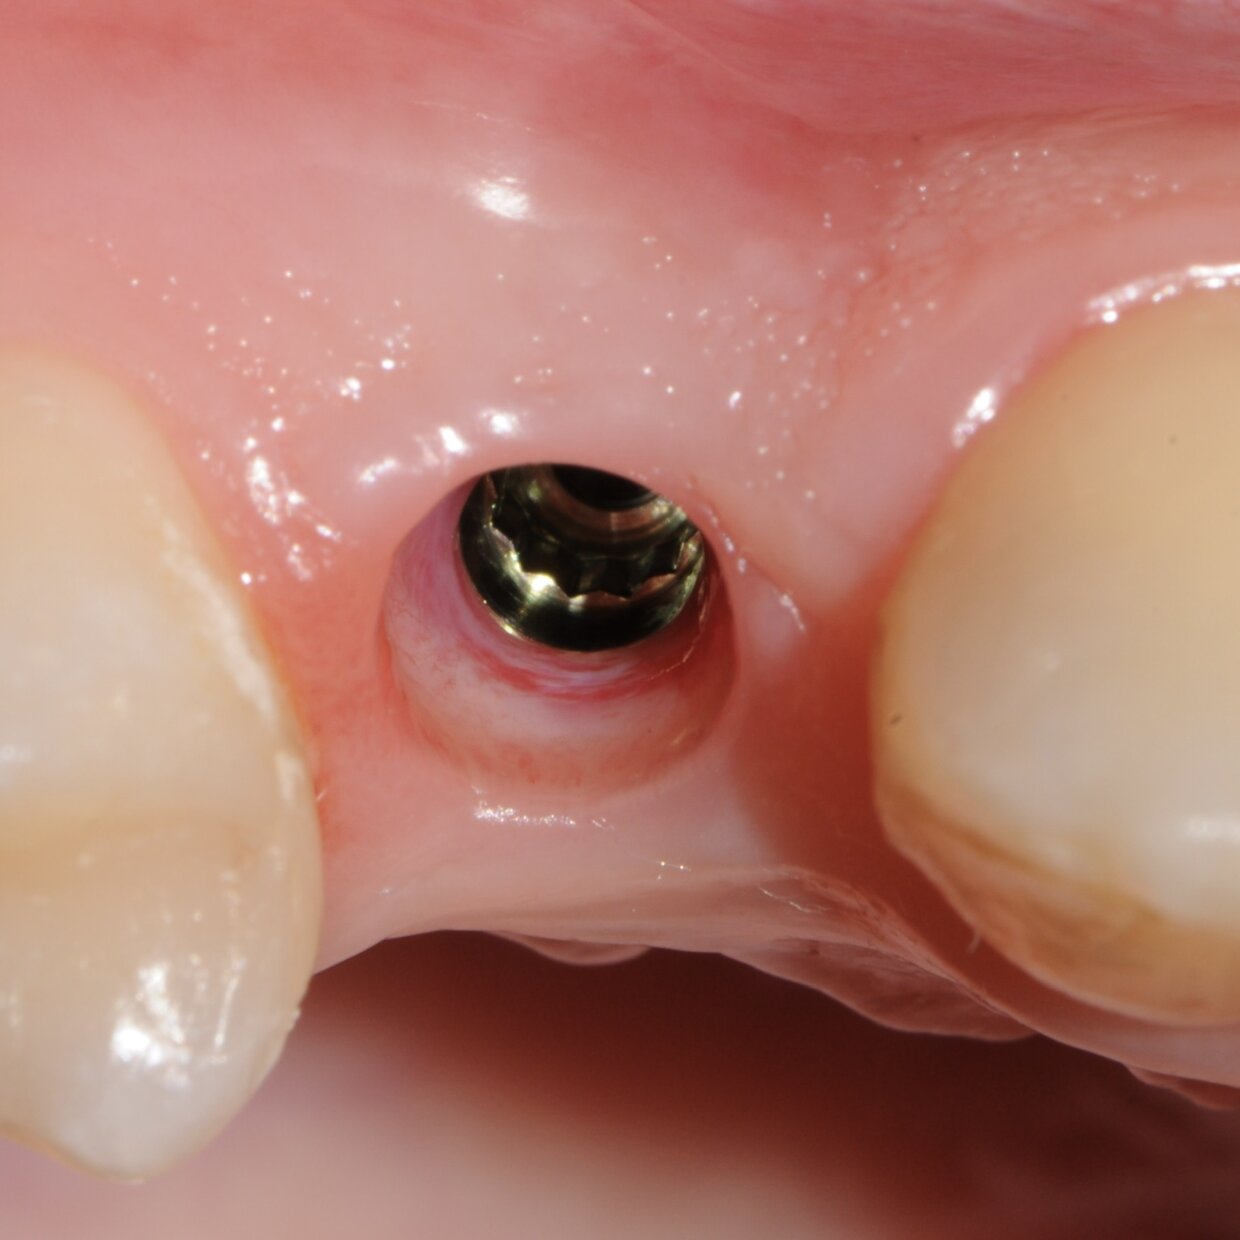

Impianto con tecnica Flapless

Minimamente invasivo, senza lembo chirurgico nè punti di sutura

Il posizionamento degli impianti è stato pianificato prima dell'intervento su un software dedicato. In un'unica seduta, dopo l'estrazione degli elementi dentari compromessi, sono stati immediatamente inseriti gli impianti nella posizione pianificata, grazie alla realizzazione della dima chirurgica. Per ridurre il riassorbimento osseo a lungo termine e garantire quindi una maggiore resa estetica (vista la zona d'intervento), la chirurgia è stata eseguita con una particolare tecnica denominata: Socket Shield Technique.